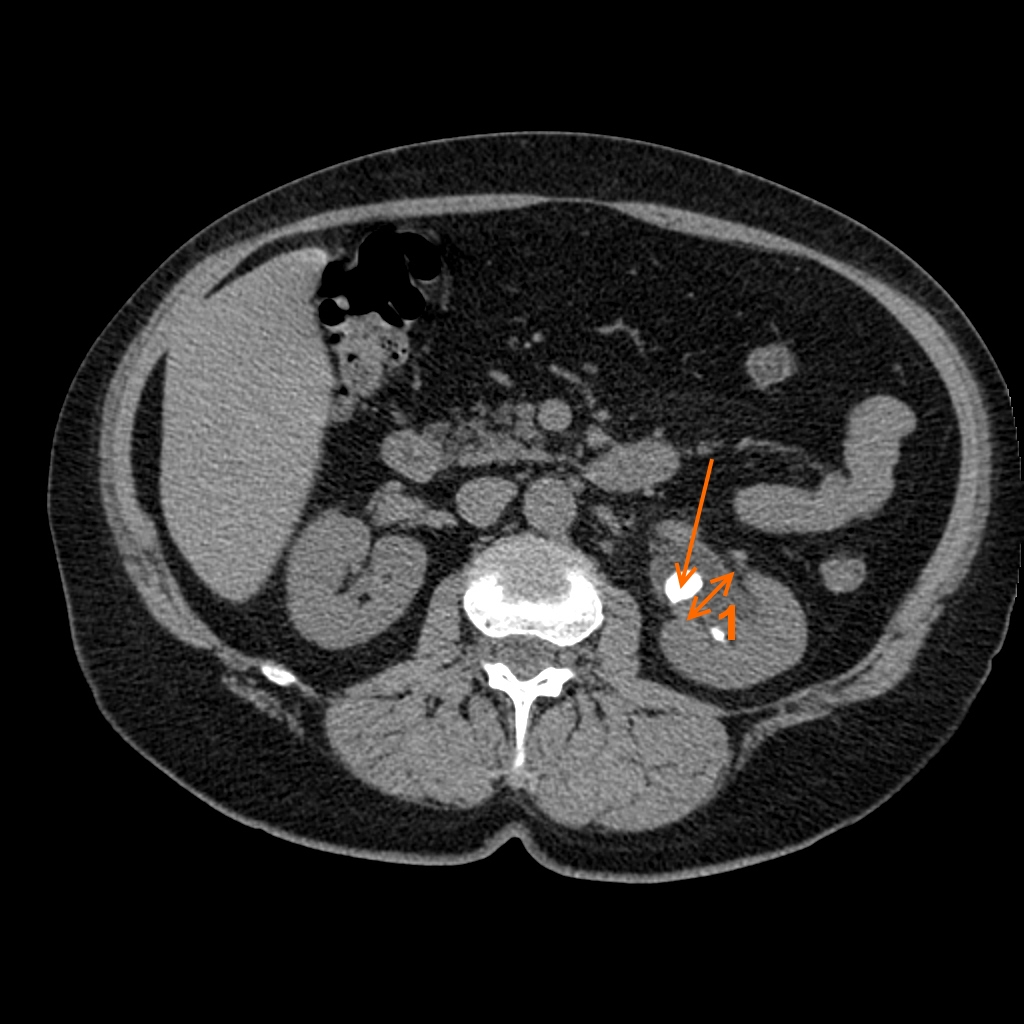

Фотографии и снимки КТ легких без контрастных веществ

Раздел: Визуальный дайджест